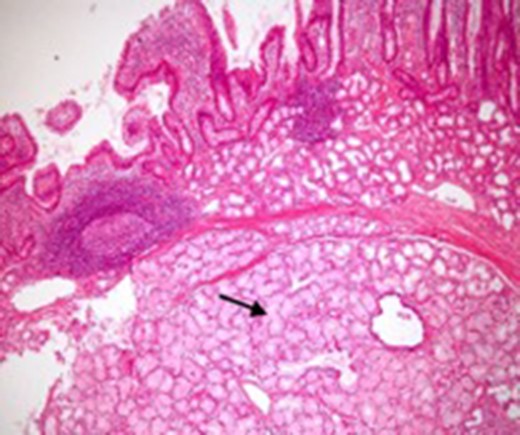

Microscopic appearance of Brunner’s gland hyperplasia. Arrow pointing at Brunner’s glands in the submucosa (stained by H & E).

Endoscopy can localize the lesion; however, biopsies are usually negative. Only a deep endoscopic or a surgical biopsy provides adequate tissue because the Brunner’s gland proliferations are usually covered by normal mucosa [10] (Figs 6 and 7). It is prudent to include a Brunner gland hyperplasia in a differential diagnosis while evaluating a duodenal mass, since it has varied presentation and bleeding is a common clinical sign masquerading other gastrointestinal conditions, e.g. gastrointestinal stromal tumours.